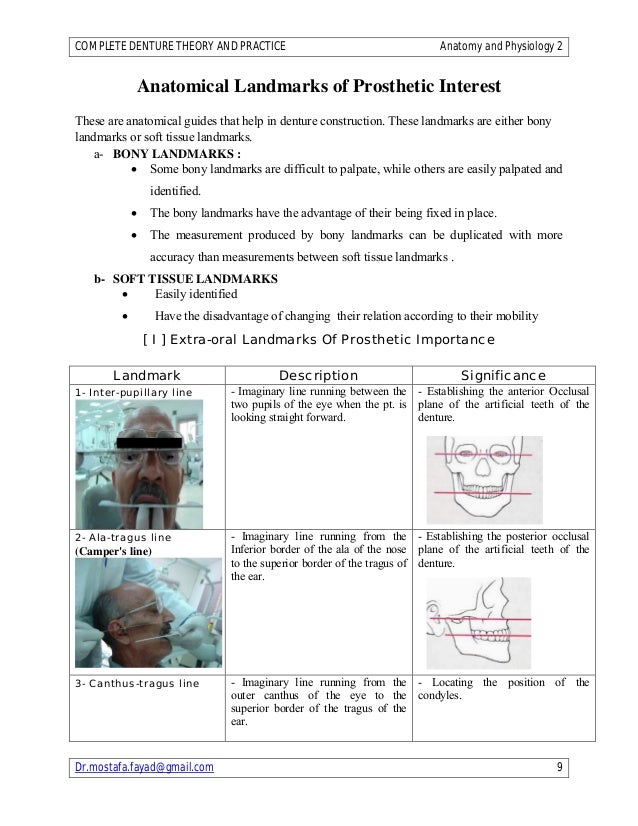

Tragus of the ear must be aligned with the plastic guides ala tragus line should be 50 from level positioning the patient position the patient panoramic lead apron must be used position apron high in front to protect the thyroid apron should be lower in back to expose the neck. Discussion most panoramic x ray machines use the ala tragus line for patient positioning whereas a few use the orbito meatal line. Ala tragus line is one of the common extra oral soft tissue land mark utilized in dental clinics for occlusal plane orientation. Here the occlusal plane should be mildly curved upward to make a smile like line.

The ala tragus line as a guide for orientation of the occlusal plane in complete dentures 1carole abi ghosn 2carla zogheib. The smile line will also be lost. An imaginary plane or line from the ala of the nose to the tragus of the ear. The part of a panoramic x ray machine where the cassette is positioned for exposure.

The angle between this line and the horizontal plane is 3on the panorex and 4on the. Focal trough layer that area between the x ray source and the image receptor that will be imaged distinctly on the panoramic. In other words the ala of the nose should be slightly inferior to the height of the tragus. These zones are as follows.

Important in determining the correct position of the patient s head. Exposure was 80 to 90 kv at 10 ma for 1 5 to 2 seconds in accordance with the subject s physical. The panorex i s. To achieve the correct vertical angulation the head must be positioned upright and symmetrical with the ala of the nose just inferior to the height of the tragus.